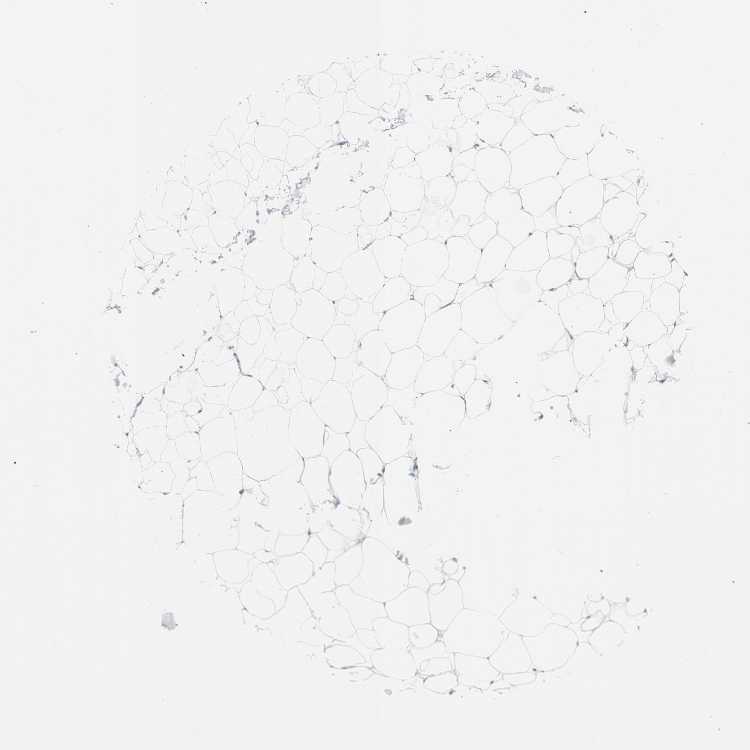

SOFT TISSUE 1 - Antibody stainingi

Antibody staining in the annotated cell types in the current human tissue is reported as not detected, low, medium, or high, based on conventional immunohistochemistry profiling in selected tissues. This score is based on the combination of the staining intensity and fraction of stained cells.

Each image is clickable and will lead to virtual microscopy that enables deeper exploration of all samples and also displays staining intensity scores, fraction scores and subcellular localization as well as patient and tissue information for each sample.

Antibody HPA009081Antibody HPA009173Antibody CAB025004

Chondrocytes HighNot detected-

Fibroblasts Not detectedLowNot detected

Peripheral nerve --Not detected